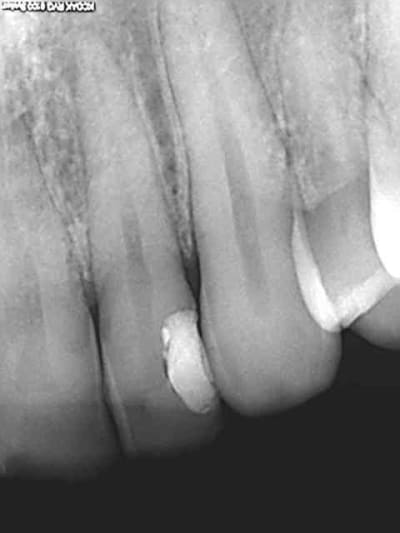

Le patient est content aussi. J'avais pas mal avant et j'ai eu mal après surtout au froid, je suppose que le confrère a gardé cette 22 vivante pour l "arranger". Je lui ai fait un test de vitalité au cryospray, ca s'arrange en effet, plus de réponse !))))

> Oui mais maintenant tu feras l'endo dans de bonnes conditions. La dent est parfaitement étanche coronairement, tu poses la digue dans les règles de l'art. :-P

Très honnêtement, quand je sais que je ne fais que "préparer la dent" pour la future endo, je monte les parois au verre io, et HN. En revanche quand je lui laisse une chance avec fond de cavité et tout...je prends royalement mes 40,97...

Et si cela ne dure que 2 mois, so be it. J'aurais tenté le coup, et je dors bien.

Tu rigoles ? déjà que le patient se plaignait de la douleur au froid suite au précédent traitement et n'était pas content de son précédent praticien à cause de ça, je vais attendre bien gentiment qu'il se pointe avec une bonne pèche. Je vais passer passer pour le bon dentiste qui soulage et pas pour le provocateur de douleur.

Ps : soit c'est gratuit soit tu cotes. En aucun cas hn pour une restauration qui peut être provisoire. Dors bien si tu as un contrôle ss au moins tu auras pris de l'avance. Prendre du HN sur un soin qui risque de partir en pulpite ,faut oser.)))))